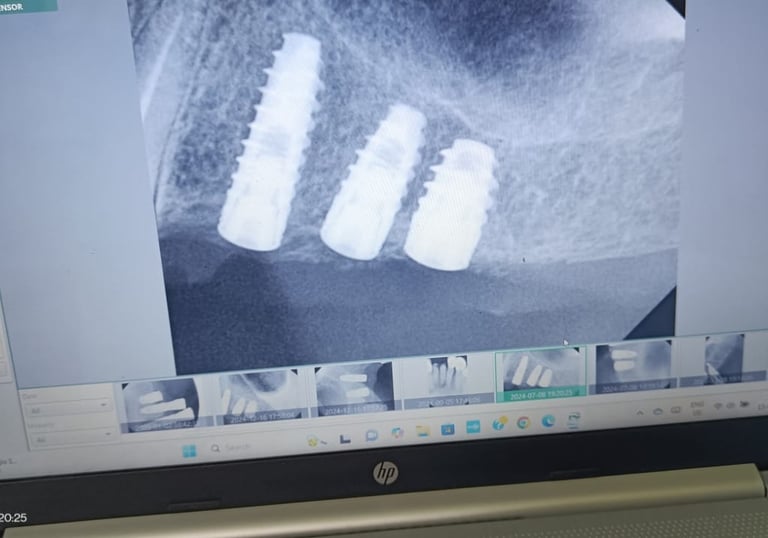

Dental Implants

Permanent replacement of missing teeth with natural-looking and durable implants for improved function and aesthetics.